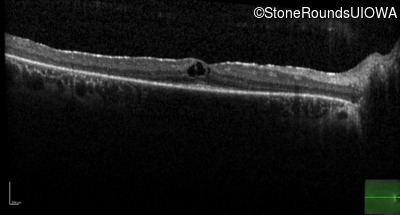

Optical Coherence Tomography - Left -

20/20 -2

Exemplar / OCT Stack